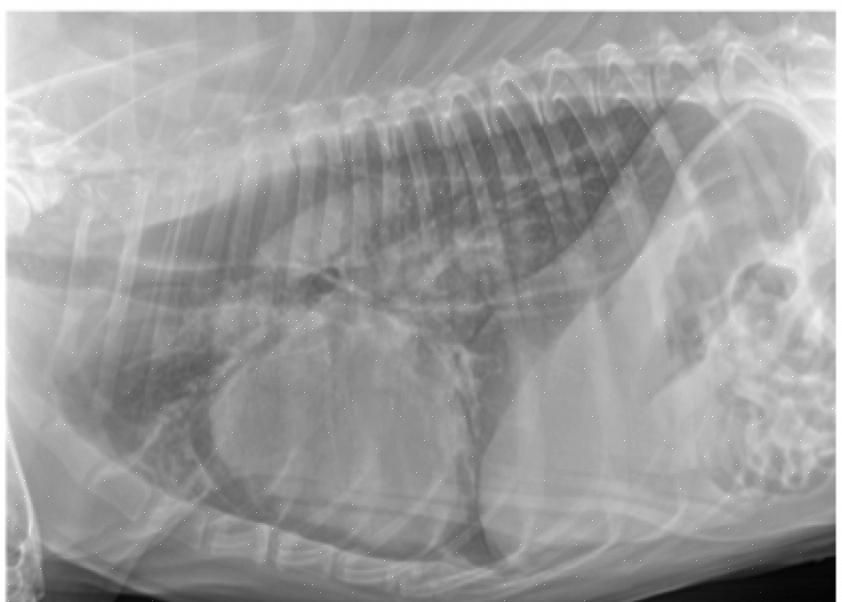

Ved ankomst til veterinærkontoret vil det bli utført en fullstendig undersøkelse av hunden din som vil inkludere å lytte til hjertet gjennom et stetoskop. I de fleste tilfeller brukes røntgenbilder av thorax (røntgen) for å diagnostisere alle former for lungeødem. Hvis det oppdages et hjerteproblem, vil behandlingen begynne med ekstra oksygen, hvile og administrering av Lasix (furosemid), et vanlig vanndrivende middel.